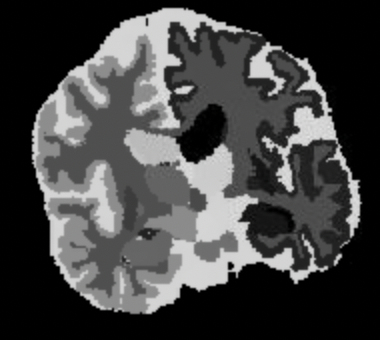

Here, we use both the INU model described in Equation 7 and the homogeneous noise model described in Equation 8. For the former, we use random fields with increasing spatial frequency (). We denote the corresponding learnable parameters , and , with preset values . Noise-free target “real”, and learned images are shown in Figure 2. Inference results for the value of the noise parameter are reported in Table 3, and are in line with those obtained in the noise-only experiment.

| (a) Noise-free image | (b) Learned image | (c) Real image |